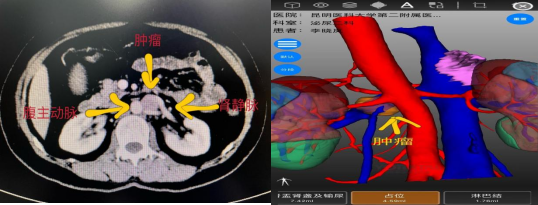

该患者既往行左肾上腺解剖性切除术,本次体检发现左侧腹膜后占位性病变,发现后患者在家人的陪伴下慕名前来樱花动漫 泌尿外科二病区杨德林教授门诊就诊。患者入院后,杨德林主任团队对其病情进行详细研判后发现,该占位性病变位置非常特殊,位于腹主动脉、左肾静脉、左肾动脉之间,与左肾静脉关系尤为密切,肿瘤位置较深,周围血管关系复杂,手术难度极大,术中稍不注意就可能导致周围血管的损伤从而影响重要器官的功能。若从肿瘤位置观察经腹膜后可能相对更好显露,但患者既往有手术病史,经腹膜后途径可能粘连严重。因此,经过综合考量后,团队决定积极做术前准备,手术采用机器人辅助下经腹入路。

术前影像学检查

在狭窄的空间面对极其脆弱的人体器官,既要保证不损伤血管,又要将肿瘤完整切除,对医生手术时牵拉的力度及精细操作程度都要求极高,这也极大地增加了本次手术的难度。